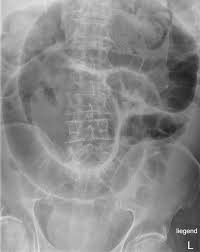

Intestinal obstruction occurs when the normal flow of digestive contents is partially or completely blocked in the small or large intestine. This is a serious condition that requires prompt medical evaluation and timely intervention to prevent complications like bowel ischemia or perforation.

Potential causes include:

• Previous abdominal surgeries causing adhesions

• Hernias, strictures, or inflammatory bowel conditions

• Tumors or impacted masses within the bowel

• Volvulus (twisting of the intestine) or intussusception